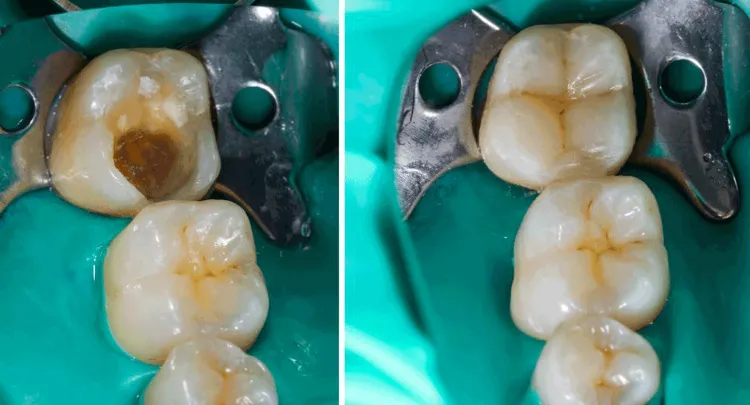

Dental Fillings Before And After